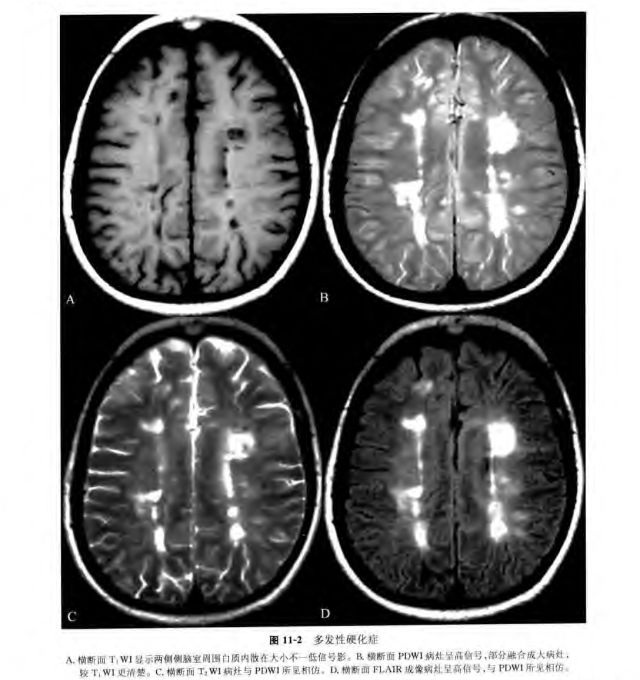

多发性硬化的康复治疗

独特成像:t1磁化传递对比成像在多发性硬化中的应用